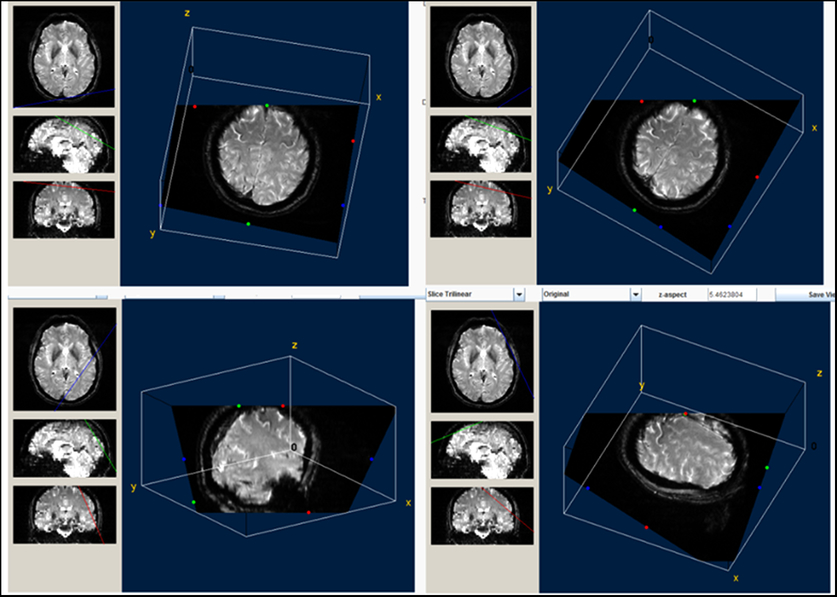

Figure 3: Three-dimensional view of the precentral black ribbon. This reconstruction is very useful to visualize the extent of the ribbon and its somatotopic representation.

We evaluated the presence of a “black ribbon” (BR) of low signal intensity using the same technical conditions and parameters described above. Briefly, a standardized T2-weighted sequence was used to acquire fine axial image slices on the 3T device. Three independent observers used two different types of software to score the area and signal intensity in the demarcated precentral region. After analyzing the consistency of visual interpretations on DICOM-MIR and/or OSIRIX in an ordinal scale (0 = no BR, 1 = discrete BR, 2 = evident BR, and 3 = marked BR), results were validated by first analyzing the precentral images with a 3D builder software that allows the measurement of the low intensity peaks and subsequently with Image J software (U.S. National Institutes of Health, Bethesda, Maryland, USA) (Figure 1). Eight-bit gray-scale images were adjusted to brightness/contrast of 10/850. Contour detection was performed under zoom to facilitate area and intensity measurements (Figure 2A). In order to analyze signal intensity in the same region in healthy control subjects, we performed 3D reconstruction of the BR to model the most implicated ROI in axial cuts 25/33, 26/33, and 27/33; 3D reconstructions were also useful to study the somatotopic representation of iron deposits (Figure 3).

BR Sign Measurement

Visual analysis of the BR yielded good intra-rater and inter-rater kappa values that ranged from 0.69 to 0.98. Visual interpretations were complemented by measurements of signal intensity in the delineated area of the sign (Figure 2A) and a ribbon model placed over the precentral region when signal attenuation was not distinguishable. A quantitative analysis of signal attenuation confirmed enhanced paramagnetic effect in 33 patients with ALS (91.66%). Patients displaying the sign presented a BR in multiple image slices (2–9 axial cuts). Inter-rater correlation for these measurements was 0.953 (p < 0.001); sample results from two observers (Y.A. and J.M.) are shown in Figure 1A. The area of hypointensity obtained by multiplying the area of each inner slice (i.e., excluding the two edges) by 3 mm yielded a mean (± standard error of the mean) area of 75.4 ± 9.0 mm3 in the left hemisphere and 84.0 ± 9.0 mm3 in the right hemisphere. The 3D reconstruction model shown in Figure 3 was used to design and position a BR paradigm ROI for further measurements, especially when the sign was discrete or invisible (e.g., in control subjects). Signal intensity under the cut-off value of 83 AUSI was able to diagnose ALS with 97% accuracy, 92% sensitivity, 93% specificity, and a predictive positive value of 0.97. The area under the receiver operating characteristic (ROC) curve of 0.95 is presented in Figure 2B.